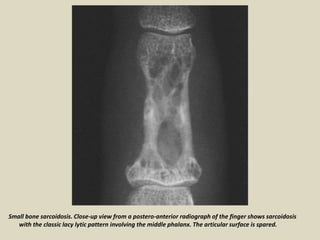

Muscle-skeletal sarcoidosis The skeleton is affected in about 1-13% of patients

with generalized disease, complaining of bone and joint pain. Sarcoidosis usually

involves the phalanges of the hands and feet; conventional radiography, performed in

symptomatic patients, demonstrate either "lacy" osteolytic or osteosclerotic multiple

lesions, where the latter is less frequent. Large bones and axial skeleton involvement

is uncommon. In large bones, lesions usually demonstrate a lytic appearance with

Small bone sarcoidosis. Close-up view from a postero-anterior radiograph of the finger shows sarcoidosis

with the classic lacy lytic pattern involving the middle phalanx. The articular surface is spared.